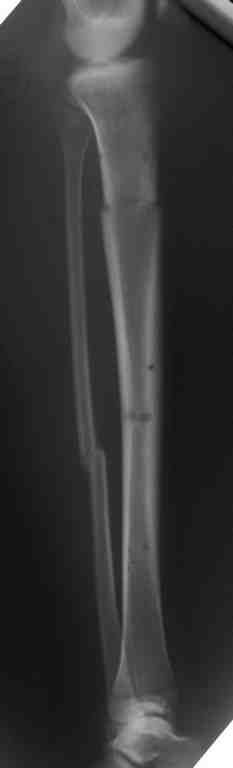

Выше приведены рентгенограммы 13-летнего подростка, страдающего от огнестрельного многооскольчатого перелома дистальной трети бедра. AO наружный фиксатор наложенный в день травмы не дал приемлемой редукции. Через три недели после перелома аппарат Илизарова был наложен без попытки одномоментной репозиции на операционном столе.

There are X-Rays of a thirteen year old boy with a comminuted distal femur fracture secondary to a gunshot wound, initially treated with an AO external fixator. The alignment was unacceptable and an Ilizarov external fixator was applied three weeks after the injury. No attempt of definitive reduction was made during the surgery.

Гексаподная приставки наложена на 10 дней и приемлемая редукция была получена.

The Hexapod set was applied for ten days and acceptable reduction was received.

По окончанию редукции Гексаподный сет был снят и дальнейшее ведение больного проходило в стандартном режиме аппарата Илизарова. Хороший анатомо-функциональный результат был получен.

When reduction was finished, the Hexapod set was removed and further management has been continued by standard Ilizarov regime. Good anatomic and functional results were achieved.